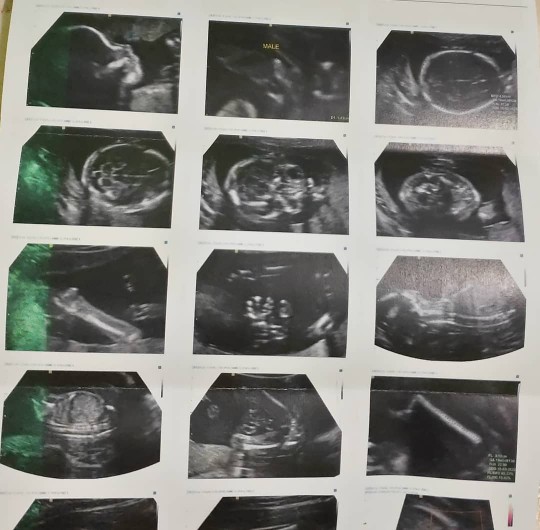

22มีค.ชายจ้า

11 มี.ค. ชายคะ

11มีนา ชายคะ

เด็กชายคร๊าบ